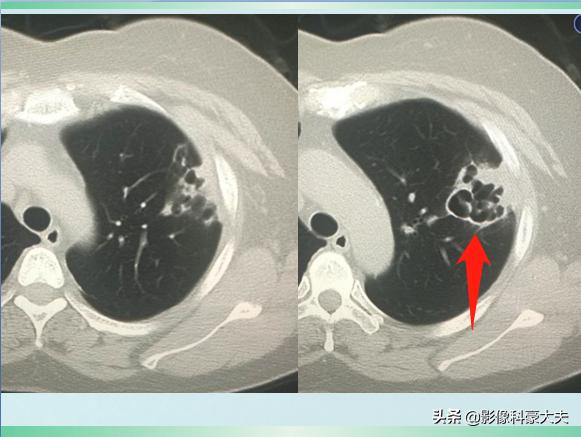

本病例来自网络

这是一位62岁的退休教师,因为淋雨受凉后出现高热、胸痛、咳嗽症状,自服感冒药无效,在家里拖了3天才过来,已经是重症肺炎,肺组织广泛坏死了,后来没有抢救回来……

这类重症肺炎的进展常常很凶猛,比癌症还厉害,早期积极治疗很关键!